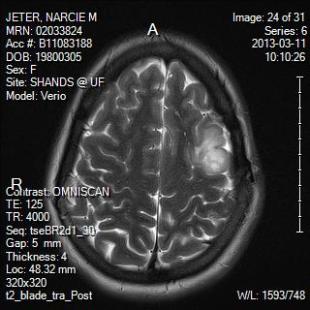

In December I had an appointment with my neurosurgeon in Charlotte and since it was the last day of classes here and was a 7 hour drive, I decided to cancel it and find a neurosurgeon here in Gainesville.  I didn’t make this decision lightly and I looked up all sorts of things about the awesome program here and I asked around to a number of people.  I saw my new neurosurgeon for the first time on Valentine’s Day (ha!).  He ordered an MRI to be done the Monday after our spring break trip to Costa Rica (March 11th).  On Tuesday, March 19th while Mike and I ate lunch with Evy, the nurse called and said that the doctor recommended surgery.  She then set an appointment for me to talk to him about this for today, March 28th.

Three years have passed since the first surgery.  To review, my doctor in Charlotte removed what he could of the tumor but left a strip near the motor cortex of the brain.  The type of tumor I have is an oligodendroglioma and very thankfully it’s a grade II (low grade).  At the time, research and common practice said that you take a watch and wait perspective and treat symptoms.  Now, research says that you resect as much as you can of the tumor so that it does not increase in grade.  They will use computer guidance to make sure that they are as precise as possible in removing as much as they can of the tumor that remains.  All of the risks associated with brain surgery are still at play here (duh.), but even more than that, because this is on my motor cortex, there could be temporary weakness in my right arm, hand and face.  As he said, scenario A is much like the first surgery – I come in on Friday and have surgery, I go home on Sunday, and I go back to work on Wednesday (this is also because I’m a crazy person that likes to work – yes, I know).  Scenario B is I go into surgery on Friday, hopefully still leave on Sunday depending on some things, go back to work in two weeks, and then possibly do physical therapy and rehab for a month.  If removing as much of the tumor as possible gives me a higher means of this not turning into something worse, I’m willing to risk either scenario.  The doctor’s suggestion is to take the “earliest elective opportunity” to do the surgery.

For those visual people out there that want to pray over an image….rock on.

Image